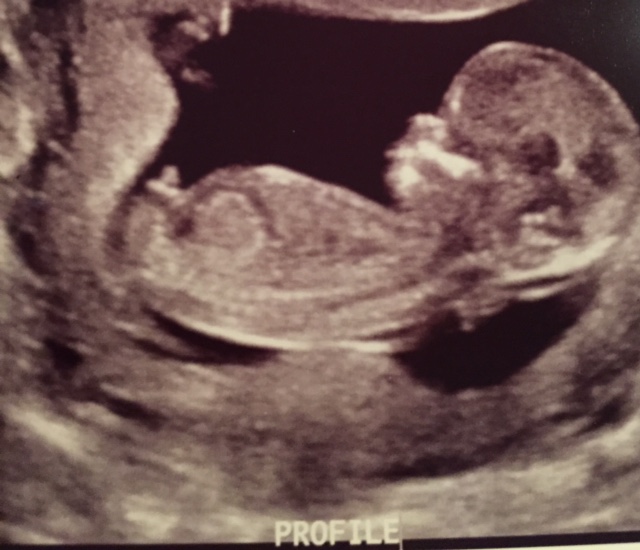

13 w, 1 d U/S - I see boy, would love guesses!

So my ultrasound tech would NOT budge on guessing boy or girl. But, I saw in between the legs what looked to be a pretty significant scrotum. No white lines of any kind. Then, we got these profile shots below. I said to her, "That's a penis." She just smiled. She wouldn't go back to the in-between-the legs shot for another glimpse. When I saw my OB and repeated my opinion, she said, "That's not a penis. It's too soon to tell either way." (She's very conservative about these things). But tell me that's not a little turtle head looking thing!

FYI: I have two boys who also had very similar skull shapes (box shape). I was swaying for girl, but I feel like this has depleted any hope of that.

The baby has its legs up in the air, as you can see in one of the pictures. Guesses please!